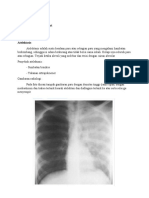

Gambar

1.4 Pemeriksaan Funduskopi